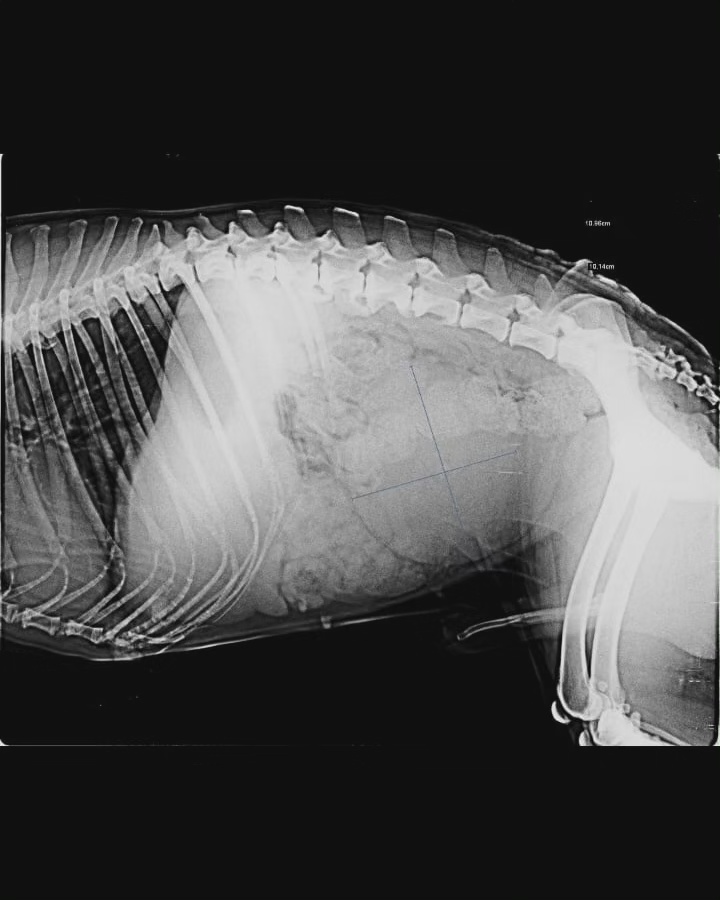

This is Lalu.

After investigation it is found that he has a tumor in his bladder almost as big as his bladder.